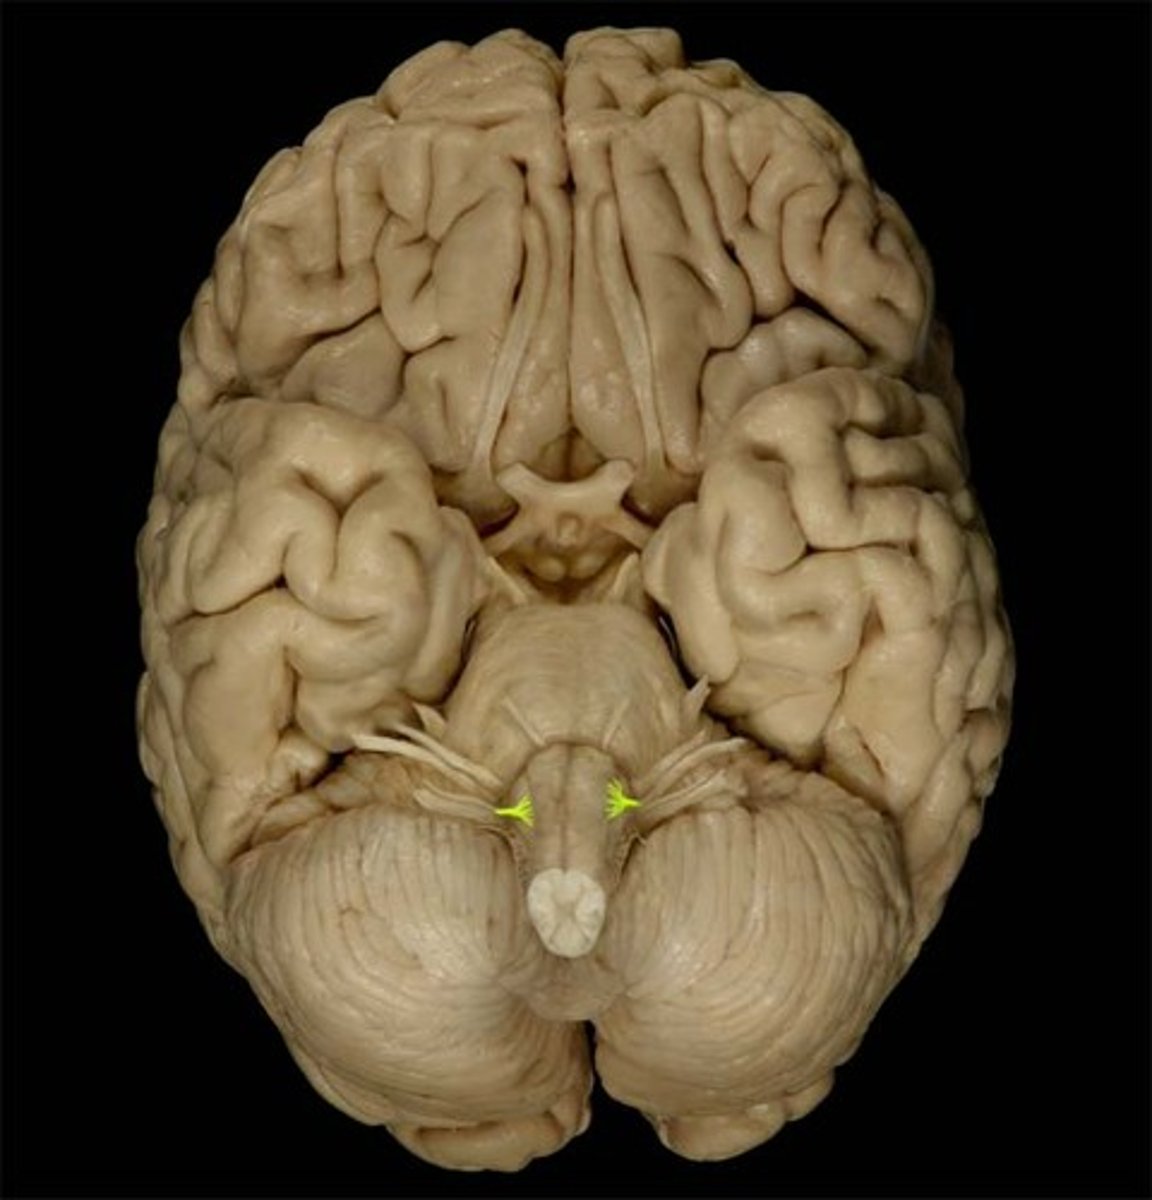

Caudate Nucleus

Globus Pallidus

Putamen